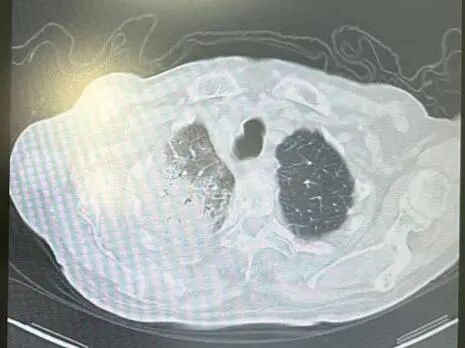

内容提要 近日,市第二人民医院呼吸与危重症医学科宋刚主任团队,成功救治一名98岁高龄、患有罕见隐源性机化性肺炎(COP)的患者。面对高龄、病情复杂、诊治风险高等重重困难,团队凭借精湛医术与丰富经验,帮助老人转危为安,再次彰显了科室在危重症救治领域的强大实力。 挑战一:高龄禁区,敢为人先 患者因发热、咳嗽,伴乏力、气短、喘息等症状来院,此前在当地诊所使用多种抗生素均无效,病因成谜。要明确诊断,支气管镜检查是关键一步,但对近百岁老人而言,此项操作犹如踏入“生命禁区”,风险极高。宋刚主任团队没有退缩,在全面评估、周密预案、充分沟通的基础上,凭借丰富经验成功实施检查,为后续治疗打开了至关重要的突破口。 治疗前患者肺部CT影像 挑战二:罕见病症,迷雾重重 检查结果指向一种罕见疾病——隐源性机化性肺炎(COP)。此病本就少见,好发于50~60岁人群,在近百岁老人中发生更是极为罕见。更为棘手的是,患者还伴有胸腔积液。COP通常表现为发热和肺部影像上的“游走性”阴影,很少合并胸腔积液,这使得诊断工作如雾里看花,难度倍增。 挑战三:病菌分辨,生死抉择 诊断刚明,新的考验接踵而至:患者标本中检出了根毛霉菌。COP的核心治疗是糖皮质激素,若根毛霉菌是致病菌,激素可能引发真菌扩散,用药无疑将导致致命风险。因此,辨别其是“定植菌”还是“致病菌”,成为治疗成败的关键。 宋刚主任团队凭借丰富的临床经验和严谨的诊疗思维,结合患者肺部影像特征、症状及化验结果,综合判断认为该霉菌属于定植菌,从而排除了治疗障碍,确保了后续用药安全。 精心施治,百岁老人转危为安 在后续治疗中,团队如履薄冰,精细平衡抗凝与激素治疗带来的出血、感染等风险,制定个体化方案。经过精心治疗与护理,老人肺部病灶显著吸收,各项指标恢复正常,最终康复出院。 治疗前后肺部CT影像对比,左侧为治疗后,右侧为治疗前。 此次成功救治,充分体现了市二院呼吸与危重症医学科在复杂疑难呼吸道疾病及危重症领域的综合救治能力。面对高龄高风险患者,团队始终以患者为中心,在风险与疗效间精准把握,用技术与责任守护每一位患者的呼吸健康。 人民医院 人民名医 宋刚 主任医师 ·葫芦岛市第二人民医院呼吸与危重症医学科主任 ·辽宁省生命科学学会东北呼吸与危重症医学(PCCM)分会辽宁省基层委员会副主任委员 ·辽宁省细胞生物学学会放射粒子治疗专业委员会理事 ·辽宁省抗击新冠肺炎疫情先进个人 ·辽宁省预防医学会第一届吸烟相关疾病防治专业委员会委员 ·葫芦岛市劳动鉴定委员会专家库成员 ·葫芦岛市医学会呼吸内科学分会第三届委员会副主任委员 专业特色:擅长呼吸系统疑难及急危重患者的救治,如急慢性支气管炎、支气管哮喘、慢性阻塞性肺疾病、肺炎、肺栓塞、肺癌、间质性肺疾病、睡眠呼吸暂停综合征等,尤其擅长有创无创机械通气、支气管镜下相关检查及治疗(TBNA、气道支架置入术、球囊扩张等)、全肺灌洗术等领先技术,发表国家级期刊多篇。 出诊时间:每周二、周四全天 出诊地点:门诊二楼东侧35诊室